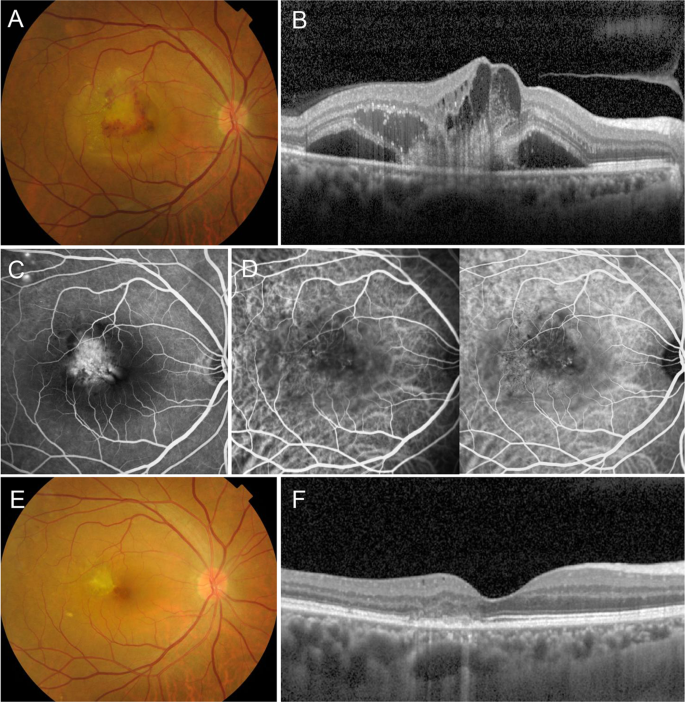

CNV

CNV Choroidal Neovascularization

Choroidal Neovascularization (CNV) is the abnormal growth of blood vessels from

the choroid (a vascular layer beneath the retina) into the retina or subretinal space.

These vessels are fragile and leak fluid or blood, causing rapid vision loss if untreated.

Diagnosis

- Optical Coherence Tomography (OCT): Detects fluid or blood under the retina.

- Fluorescein Angiography (FA): Highlights leaking blood vessels.

- Indocyanine Green Angiography (ICGA): Helps identify deeper abnormal blood vessels, especially in cases of polypoidal choroidal vasculopathy (PCV).